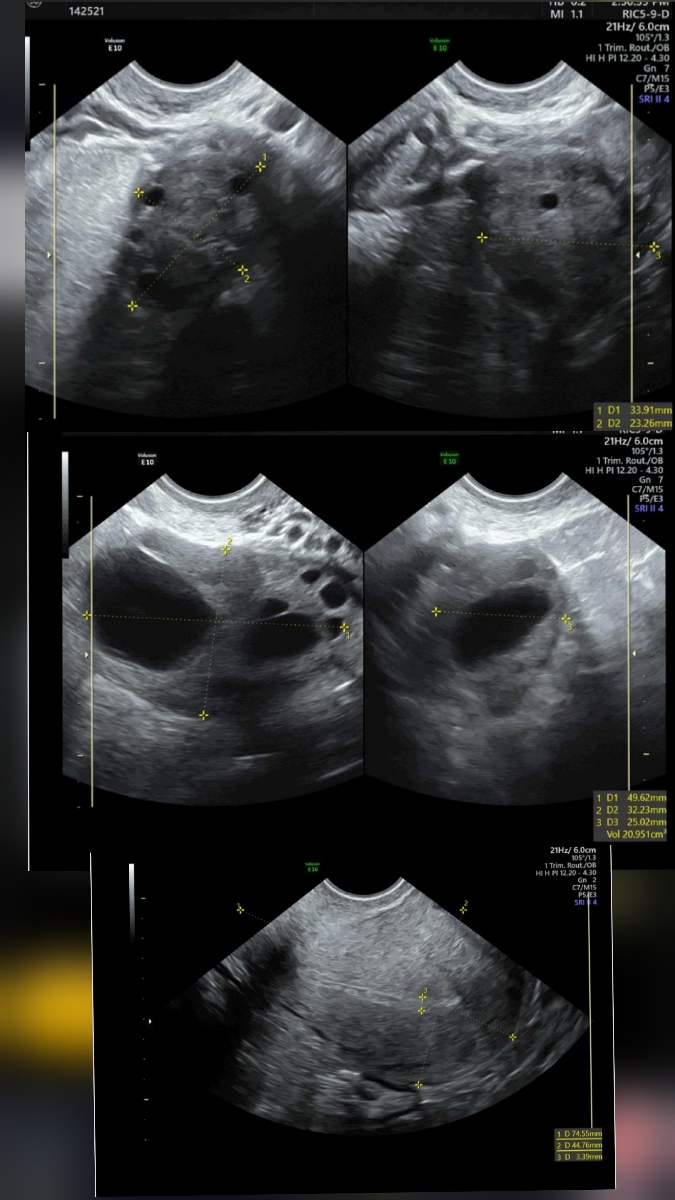

دکتر جان این سونوی جدید هست و گفتن کیست دارم

این سونو برای برج ۱هست که برای تایید epدادم و بهم گفتن کیست هم دارم

این هم برای برج ۱ به فاصله چند روز دادم چون پیش چندتا دکتر رفتم که تایید کنن هر کدوم جدا گانه فرستادن سونو

عزیزم در سونوگرافی که در زمان بارداری خوارج رحمی فرستادید در یک مورد کیستهای ریز دیده شده که همان تنبلی تخمدان است که توضیح دادم و جراحی ندارد اصلاح سبک زندگی و دارو درمانی نیاز دارد سونوگرافی آخر که ارسال کردید هم کیست در تخمدان راست بوده که برطرف شده و الان کیست در تخمدان چپ دارید بنابراین کلا نیازی به جراحی نبوده است

جانم اگر در این سونوگرافی گفتند کیست دارید این نوع کیست جراحی نمیشود چون در واقع فولیکول های شما هستند که بزرگ نشده ریز مانده کیست در نظر گرفته میشود همان تنبلی تخمدان یا سندرم تخمدان پلی کیستیک هست اگر سونوگرافی دیگری دارید که گفته کیست دارید ارسال کنید تا ببینم

الان بابت این کیست باید ال دی بخورید 3 ماه بخورید بعد اتمام سونوگرافی را تکرار کنید از نظر عفونت هم حتما معاینه شوید